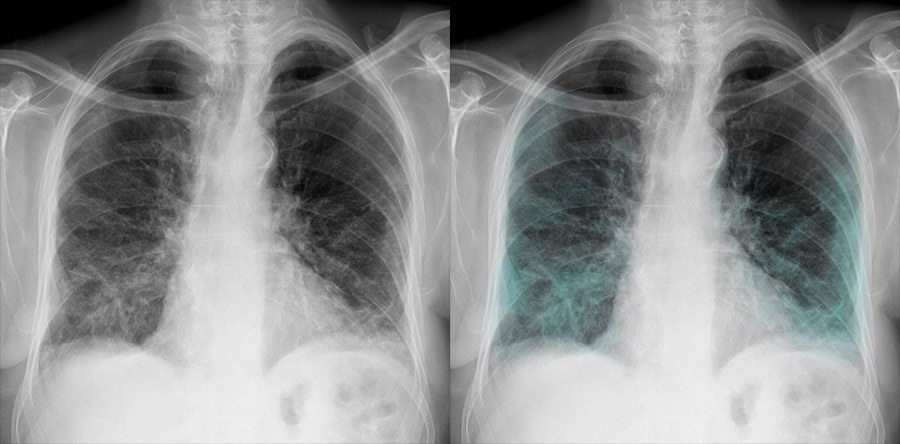

й в легких

Лей в легких 106 фотографий